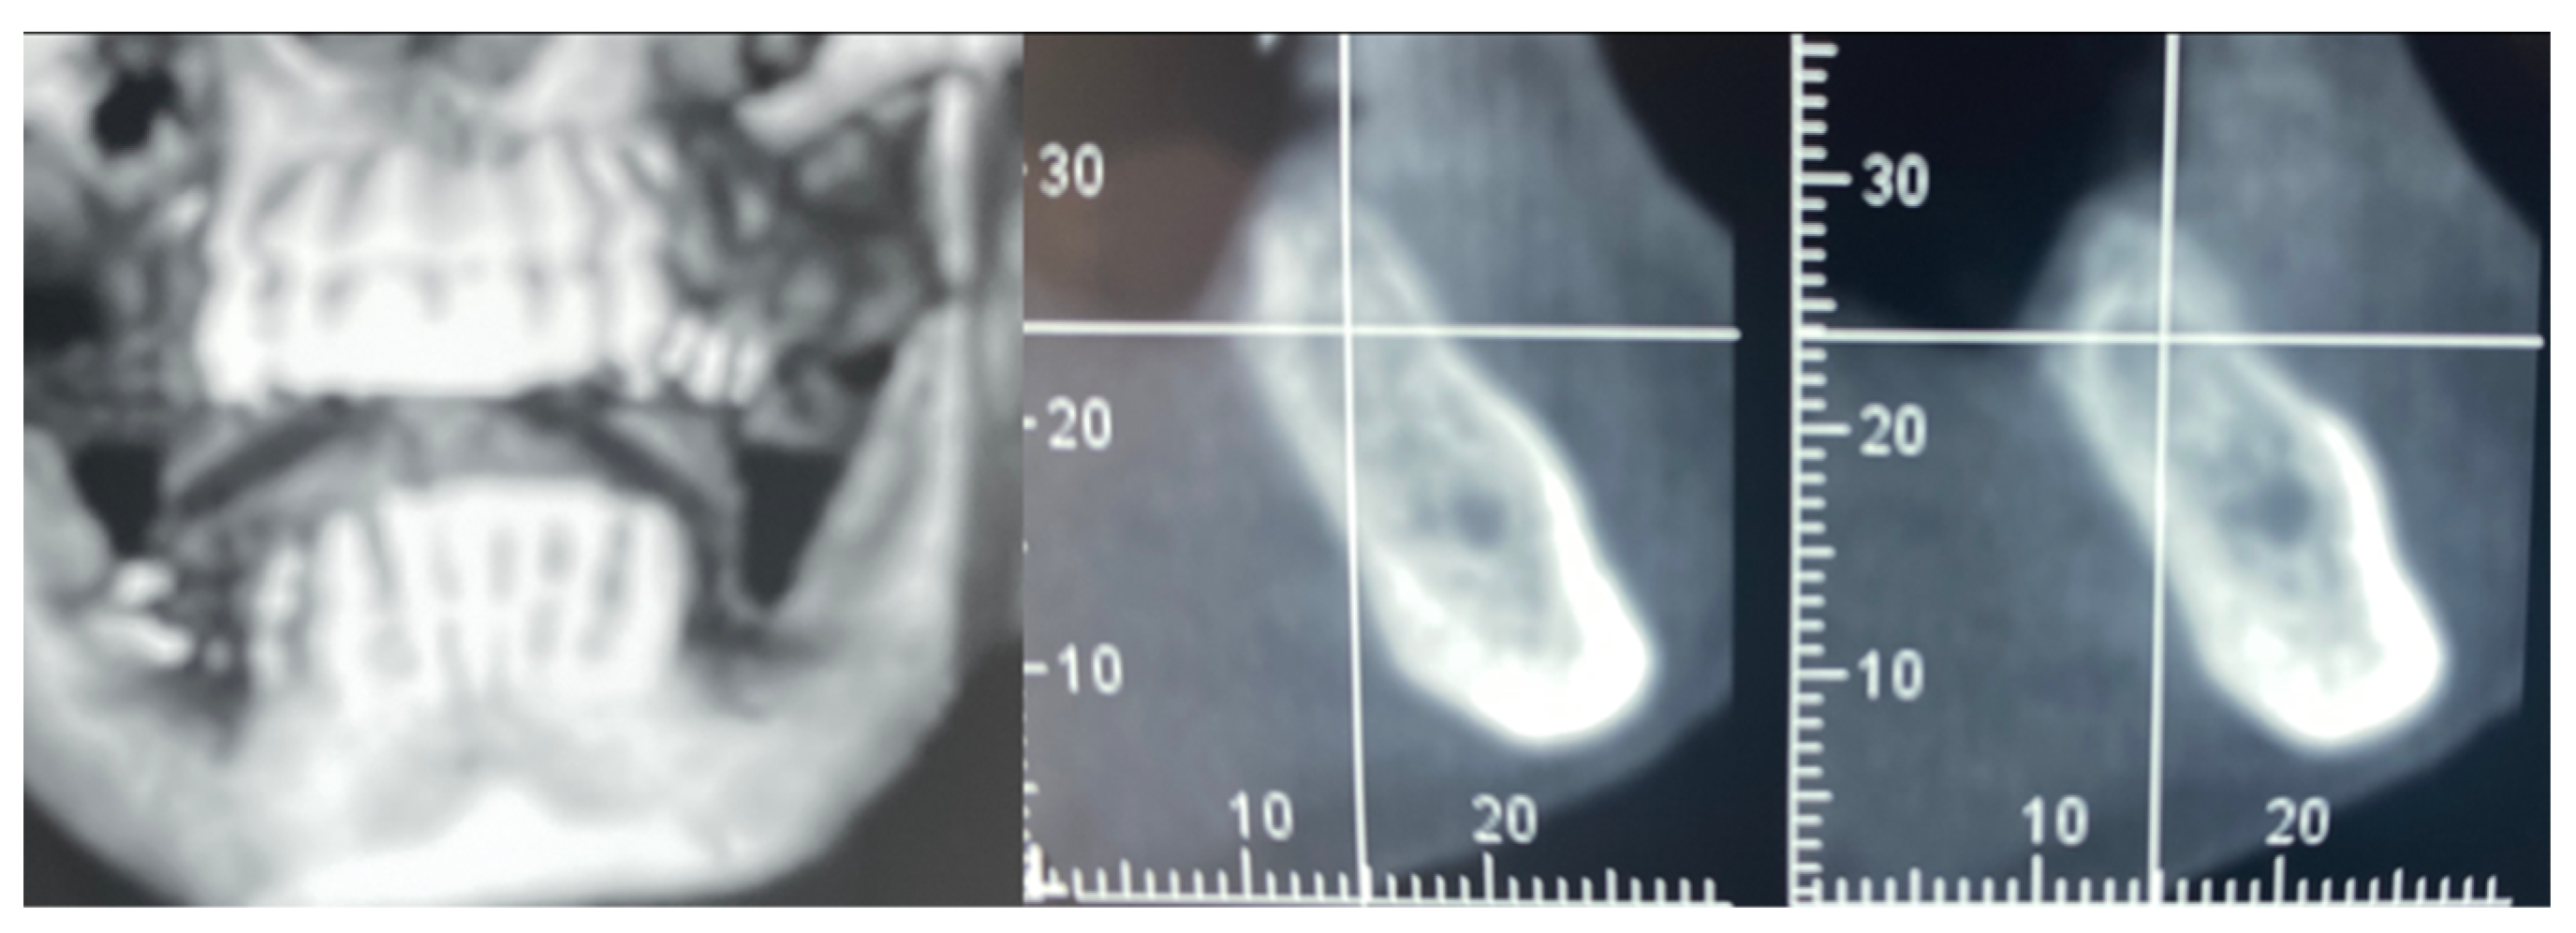

3.3. Hard Tissue Augmentation

| T2 | Guided Bone Regeneration (3 months) | GBR with Flex Cortical Sheet (Bioteck SpA, Arcugnano, Italy) |